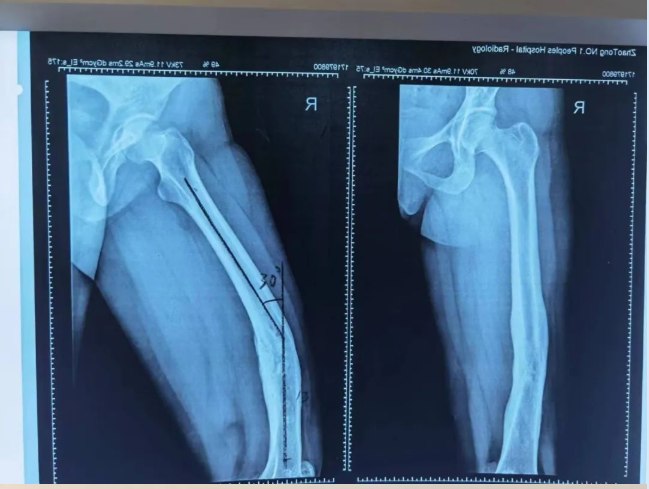

经接诊医师崔家平检查发现,患者右股骨畸形并功能障碍,右膝关节僵硬,不能活动;影像检查后发现右下肢前后及内外成角畸形明显,测量发现右侧股骨前后成角30度,内外成角19度,患者及家属急盼迅速治疗以缓解疼痛、矫正畸形。

(术前检查影像)